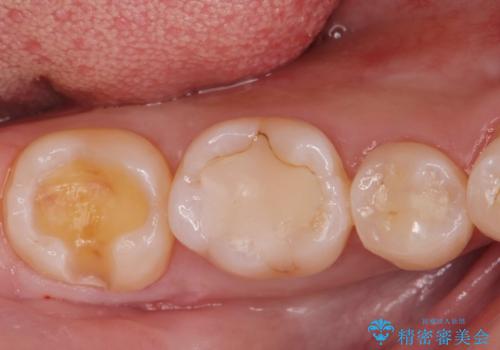

古い樹脂の劣化 セラミックインレー治療

- 保険診療での古い樹脂の劣化が気になるとの事で来院。

二つ樹脂の劣化が見られるので提案をしたが、まずは一つ治療を行いたいとの事でしたので拡大鏡下で劣化した樹脂と虫歯を取り除いた後e-maxインレーにて治療を行いました。

適合の良い詰め物が入りました。

もう一つの治療も現在検討中です。